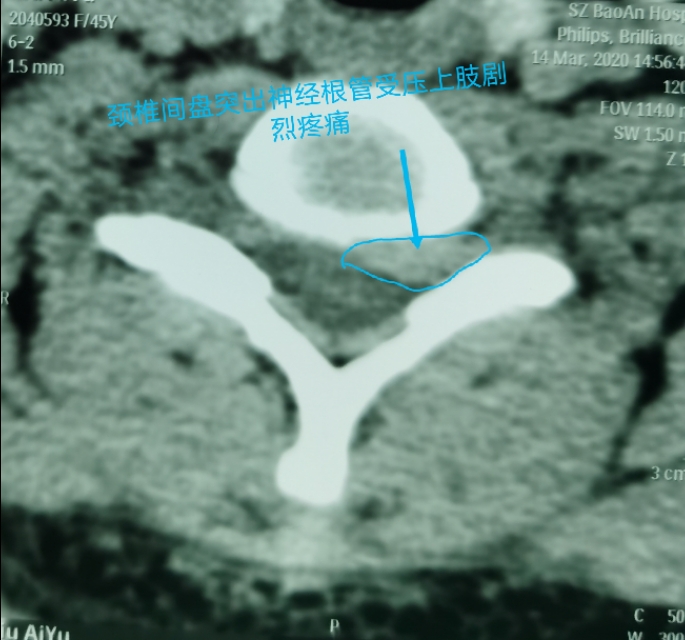

中年人疫情期居家长期卧床及长期看电脑手机,颈椎病复发今天显微镜下微创治疗,颈6-7巨大椎间盘突出.压迫神经根管,伴左上肢剧烈放射痛,显微镜下微创颈椎间盘突出治疗,用时半个小时,近零出血,取出压迫神经4块髓核,切除后纵韧带,减压至脊髓表面,脊髓恢复正常搏动,神经监护神经功能恢复好